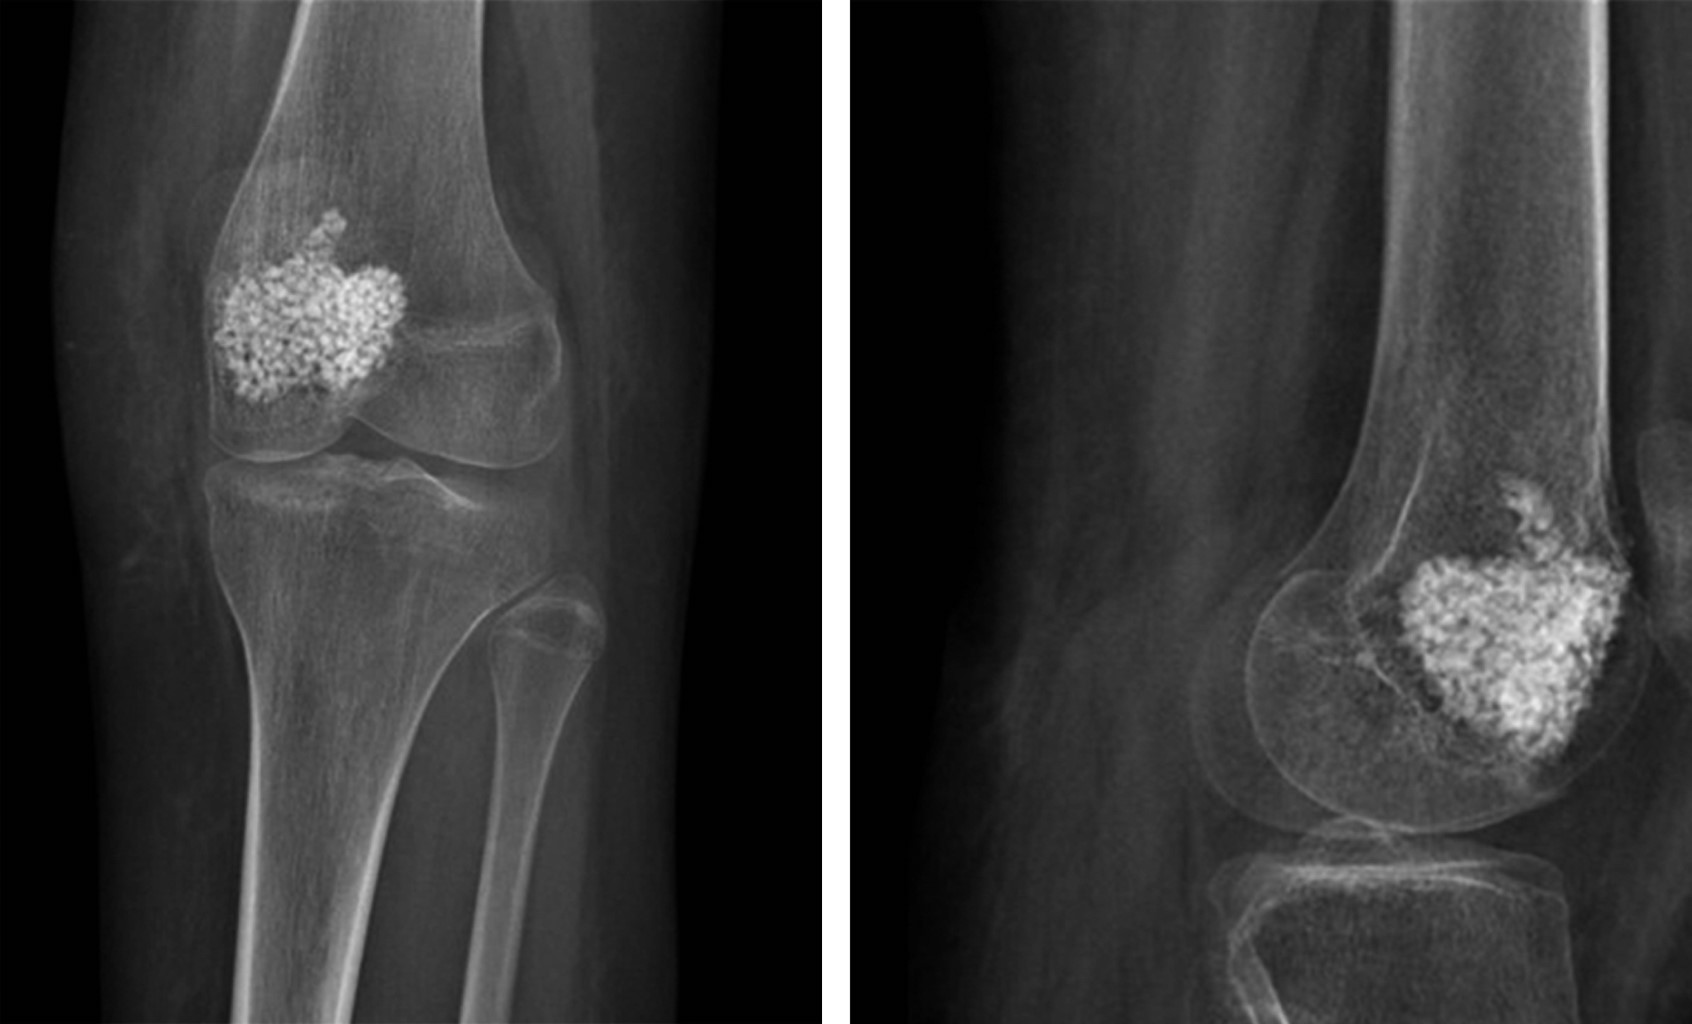

Se trata de paciente de sexo femenino de 15 años y cinco meses, sin antecedentes médicos de importancia. Consultó por primera vez en Julio de 2018 por caída a nivel en escalera, con golpe en rodilla izquierda. Evolucionó con dolor e impotencia funcional inmediata. Al interrogatorio dirigido refirió dolor de tipo insidioso desde hace seis meses, sin antecedente de trauma. Se solicitaron radiografías de fémur derecho anteroposterior y lateral en el servicio de urgencias, las cuales mostraron una fractura en fémur distal izquierdo, con sospecha de fractura en hueso patológico en la metáfisis distal de fémur con imagen que impresiona tener una lesión lítica bien delimitada, con calcificaciones centrales, rodeada por un borde esclerótico delgado sin reacción cortical, con un patrón de pop-corn similar al de un condroblastoma (Figura 1).

Se realizó el estudio complementario con TAC y RMN; en el cual la TAC de rodilla indicó una imagen lítica metafisaria de fémur distal de bordes circunscritos bien definidos con fractura en hueso patológico, sin colapso de la columna medial (Figura 2) y en la RMN en el corte T2 y supresión grasa, se observó una lesión de márgenes escleróticos sin signos de reacción perióstica, con relleno de aparente densidad líquida levemente heterogéneo, con aparente invasión fisaria, sin compromiso de partes blandas, siendo compatible con neoplasia de origen condral coincidiendo con la sospecha diagnóstica de condroblastoma de fémur distal (Figura 3).